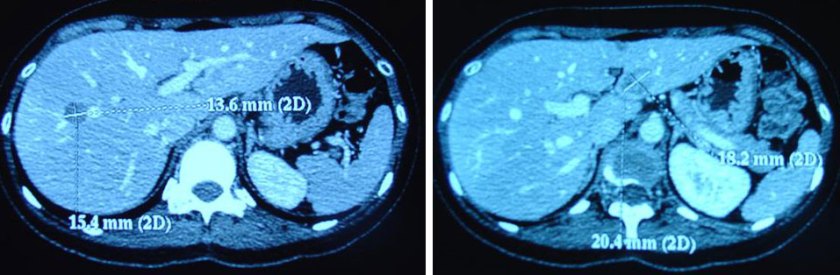

She suffered headaches, nausea and had very low blood pressure. Fransiska went back to her oncologist in August 2008. A scan showed the cancer had spread to her brain. A CT scan of the abdomen showed:

- metastasis in both hepatic lobes. The largest lesion in the left lobe measures 2.0 x 1.8 cm and the largest in the right lobe measures 1.5 x 1.4 cm.